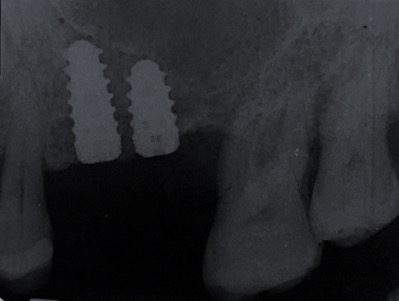

Un impianto dentale o fixture è un corpo in titanio, totalmente biocompatibile, che viene posizionato nella mascella o mandibola con lo scopo di sostituire la radice di un dente naturale perso. Su di esso viene successivamente o immediatamente quando possibile (carico immediato) fissata la protesi ovvero la corona del dente restituendo funzione ed estetica.

Gli impianti non hanno scadenza quindi non sono un rimedio temporaneo ma una soluzione definitiva per tornare ad avere denti come quelli originali. L’osteointegrazione è così forte e perfetta che se volessimo rimuovere l’impianto in un secondo momento dovremmo togliere anche l’osso che lo circonda.

Con l’implantologia oggi è possibile sostituire un solo dente come un’intera arcata anche in casi di deficit ossei grazie alla GBR (rigenerazione ossea guidata) che ci permette di intervenire quando la disponibilità ossea iniziale del paziente non sarebbe sufficiente.